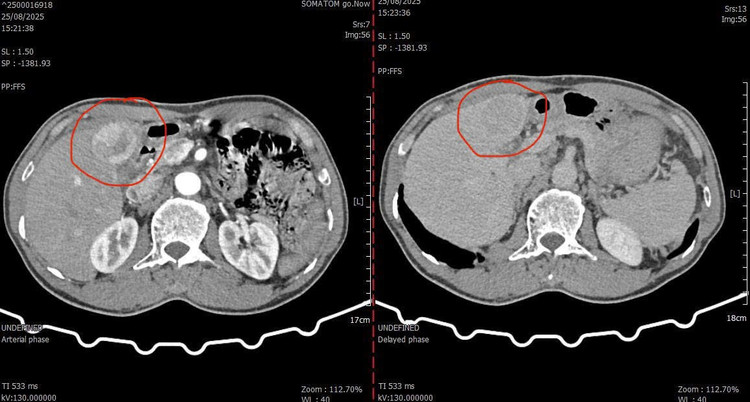

Hình ảnh khối u chụp cắt lớp vi tính trước can thiệp - Ảnh BVCC

Trong quá trình thăm khám, bác sĩ phát hiện khối u gan hạ phân thùy IV-V, kích thước khoảng 5x6 cm, giàu mạch máu – được chẩn đoán là ung thư biểu mô tế bào gan.